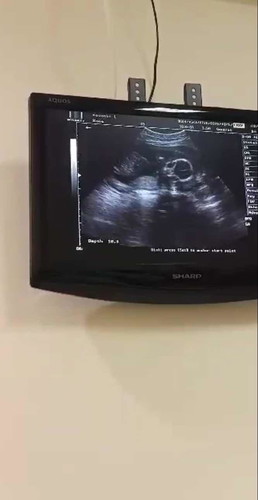

ท้องเเรกจ้าาาา อิแม่ตื่นเต้นมากเลยครั้งซาวร์ครั้งแรก🎉👩👧😘